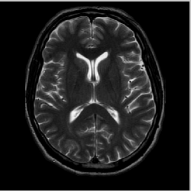

We study the performance of the proposed algorithms as a function of acceleration in the presence of noise in Fig. 3. We used a 512×512512512512\times 512 MRI brain image, sampled using a random sampling operator at different acceleration factors (R = 2.5, 4, 6, 8, 10 and 202020). The measurements were contaminated with complex white Gaussian noise of σ=10.2𝜎10.2\sigma=10.2. The PSNR and SNR as a function of accelerations of this experiment are plotted in Fig. 3, where we compare our method against DLMRI and TV. We observe that the proposed scheme provides a consistent improvement in the presence of noise.

The reconstructions of a 256×256256256256\times 256 brain image from its radial samples acquired with a 40 spoke trajectory are shown in Fig. 6. The measurements are corrupted with zero mean complex Gaussian noise of standard deviation σ=18.8𝜎18.8\sigma=18.8. All methods result in loss of subtle image features since the acceleration factor and the noise level are high. We observe that the NLS scheme provides better recovery than the competing methods. The quantitative results in this setting for various MR images are shown in the bottom section of Table IV. We observe that the SNR improvement offered by NLS over the other methods are not as high as in the previous cases, mainly due to the considerable noise in the data and the high acceleration.

Refer to caption

(a) Original

(b) DLMRI, SNR=20.46

(c) TV, SNR=22.80

(d) NLS, SNR=28.41

(e) Sampling pattern

(f) DLMRI error

(g) TV error

(h) NLS error

Figure 4: Comparison of the algorithms in the absence of noise. We consider the recovery of a 256×\times256 MRI brain image from 20% of its Fourier samples, acquired using a random sampling pattern shown in (e) using non-local shrinkage scheme (NLS), DLMRI and local TV (TV). The reconstructions are shown in (b)-(d). The corresponding error images, scaled by a factor of 5 for better visualization, are shown in the bottom row. The reconstructions show that the NLS scheme is capable of better preserving the edges and details, resulting in less blurred reconstructions.